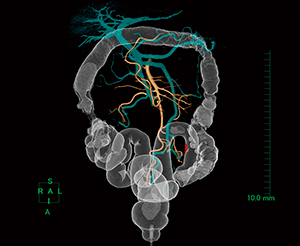

本症例では,大腸内視鏡挿入困難な潰瘍性大腸炎患者に対して大腸CT検査を行うことで範囲を知る目的があったが,中等度(粘膜粗造など)の変化を有する部位は判別できたものの,軽度の変化までは判別困難であった。CT angiography(図7)では,S状結腸動脈分岐と静脈との位置関係の情報を得ることができ有用であった。

図7 CT angiography(仰臥位)